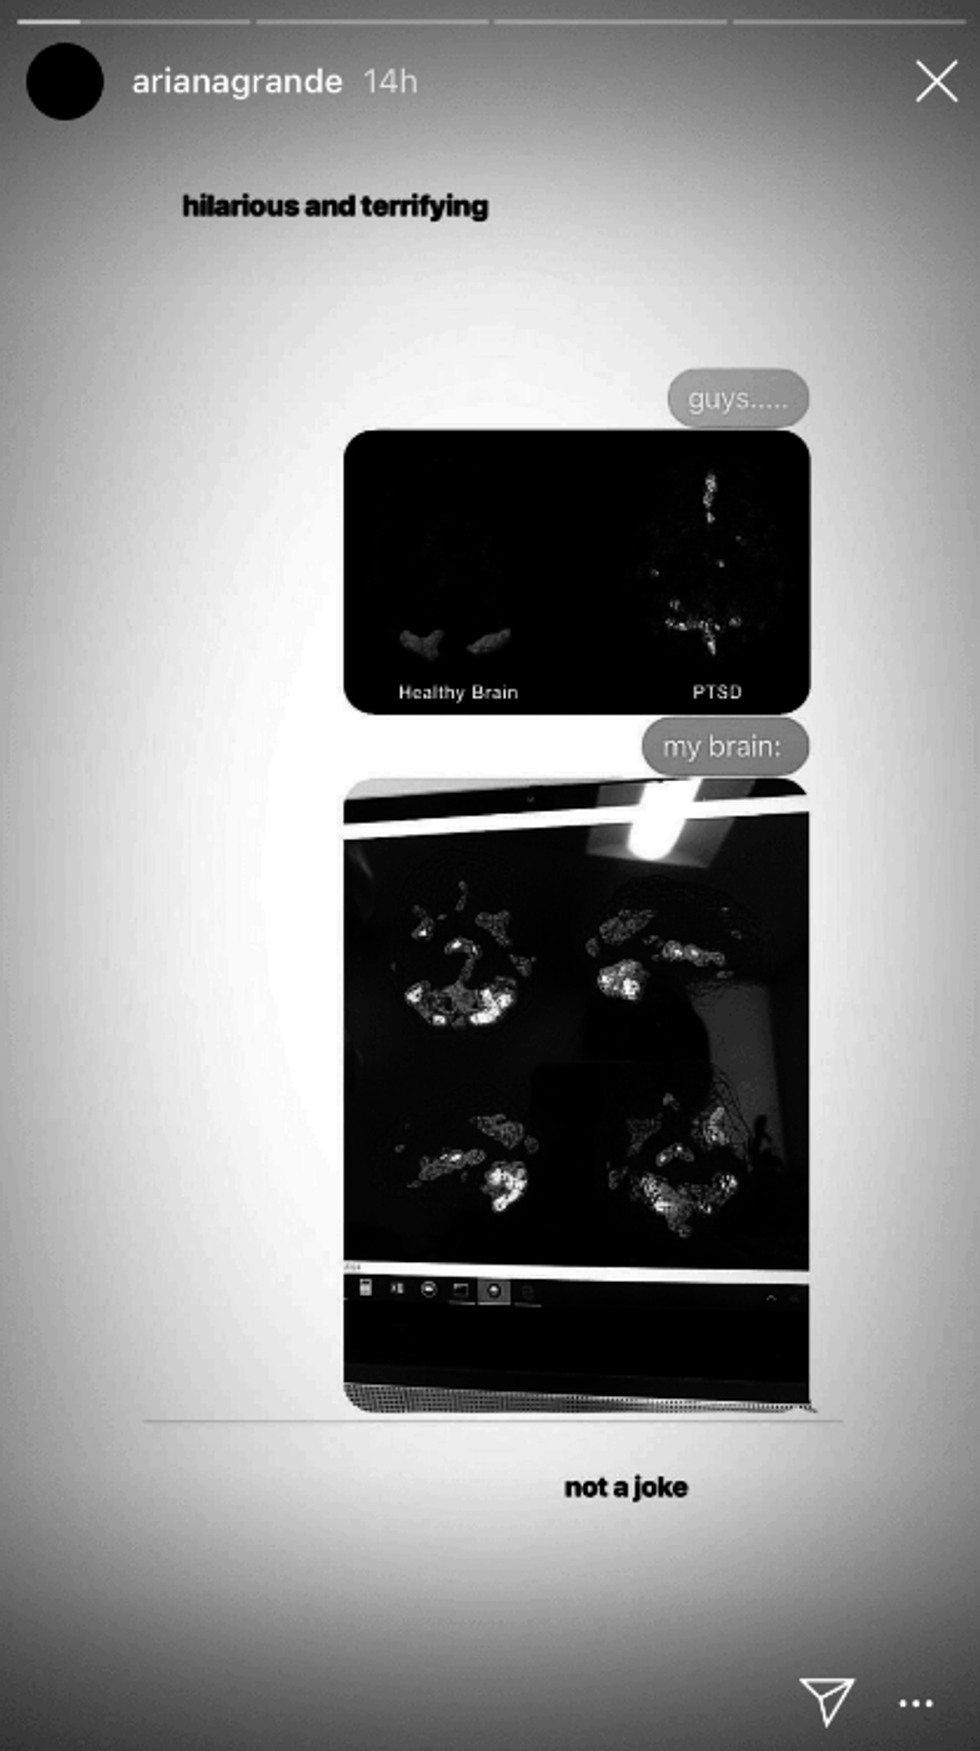

Uploading photos of side by side comparisons showing a "healthy brain" on the left next to a brain affected with Post Traumatic Stress Disorder on the right, the singer followed up with the results of her own brain scan. The photo of Grande's brain scan, like the PTSD brain, was lit up in similar regions and showed the effects of some serious hardships the artist has endured.

Having spoken out about working towards maintaining mental health after the tragic 2017 bombing of her Manchester concert, the singer's revelation is a testament to the very real effects of trauma. Grande's recent success has widened her platform for discussing this with the public and destigmatizing mental illness. Last year, she told British Vogue her PTSD was a "real thing," adding that concert-goers and fans had "a tremendous amount of it as well."

Always finding humor in the madness, the singer called the scans "hilarious and terrifying," and insisted she's "trying her muthafukin best." It goes without saying that Grande's strength is something to take note of and her openness demonstrates the very real impact that trauma has on people universally beyond entertainment.